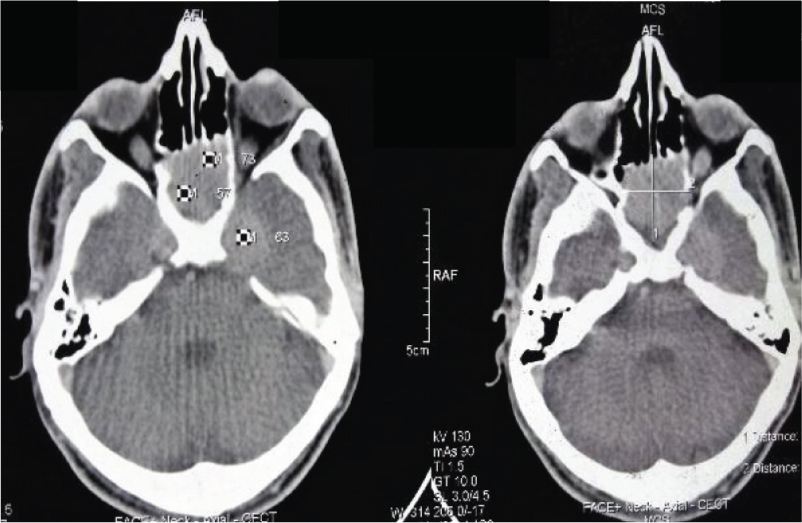

Initially, the patient received two cycles of chemotherapy with Cyclophosphamide, Adriamycin, Vincristine and Prednisolone (CHOP regimen) with progressive disease. Subsequently, a repeat biopsy was done which suggested metastatic undifferentiated carcinoma of nasopharynx. The IHC was negative for CD30 and CD68 markers and positive for cytokeratin and Epithelial Membrane Antigen (EMA). A Contrast Enhanced Computed Tomography (CECT) scan of the face and neck region showed growth in the nasopharynx infiltrating sphenoid sinuses and bulky 10 x 8 cm left cervical neck nodes [Table/Fig-1,2]. In view of the locally advanced disease, the patient was planned for neoadjuvant chemotherapy with 5FU and cisplatin followed by radical chemoradiation. However, as the disease progressed on chemotherapy showing an increase in the size of neck nodes to 14 cm x 10 cm, the patient was referred for palliative radiotherapy.

CECT film showing nasopharyngeal growth extending into surrounding structure.